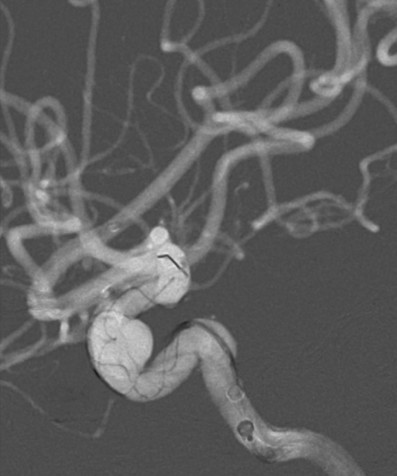

入院后行DSA检查明确右侧颈内动脉眼动脉后下方囊状动脉瘤样影,大小约1.09mm×6.53mm,宽基底,其下方见两个小囊状突起,左侧颈内动脉眼动脉后方及虹吸段均可见小囊状突起。考虑颅内多发动脉瘤。

麻醉成功后,患者仰卧,常规消毒,铺巾, Seldinger法穿刺右侧股动脉,置入5F动脉鞘,置入5F造影管行右侧颈内动脉正侧位及3D造影后,更换6F长动脉鞘,6F中间导管在导丝引导下进入右侧颈动脉分叉端并固定。根据3D造影选择工作体位并放大做路图后,T-track微导管在微导丝引导下进入右侧大脑中动脉,经微导管送入4.0×45mm Tubridge®支架,观察 Marker位置后,于颈动脉分叉附近缓慢释放支架。

Tubridge®释放过程

锚定后,整体回撤至合适位置后,通过张力释放法缓慢释放支架,直至支架完全打开。观察见支架贴壁良好,动脉瘤颈完全覆盖,遂完全释放支架。